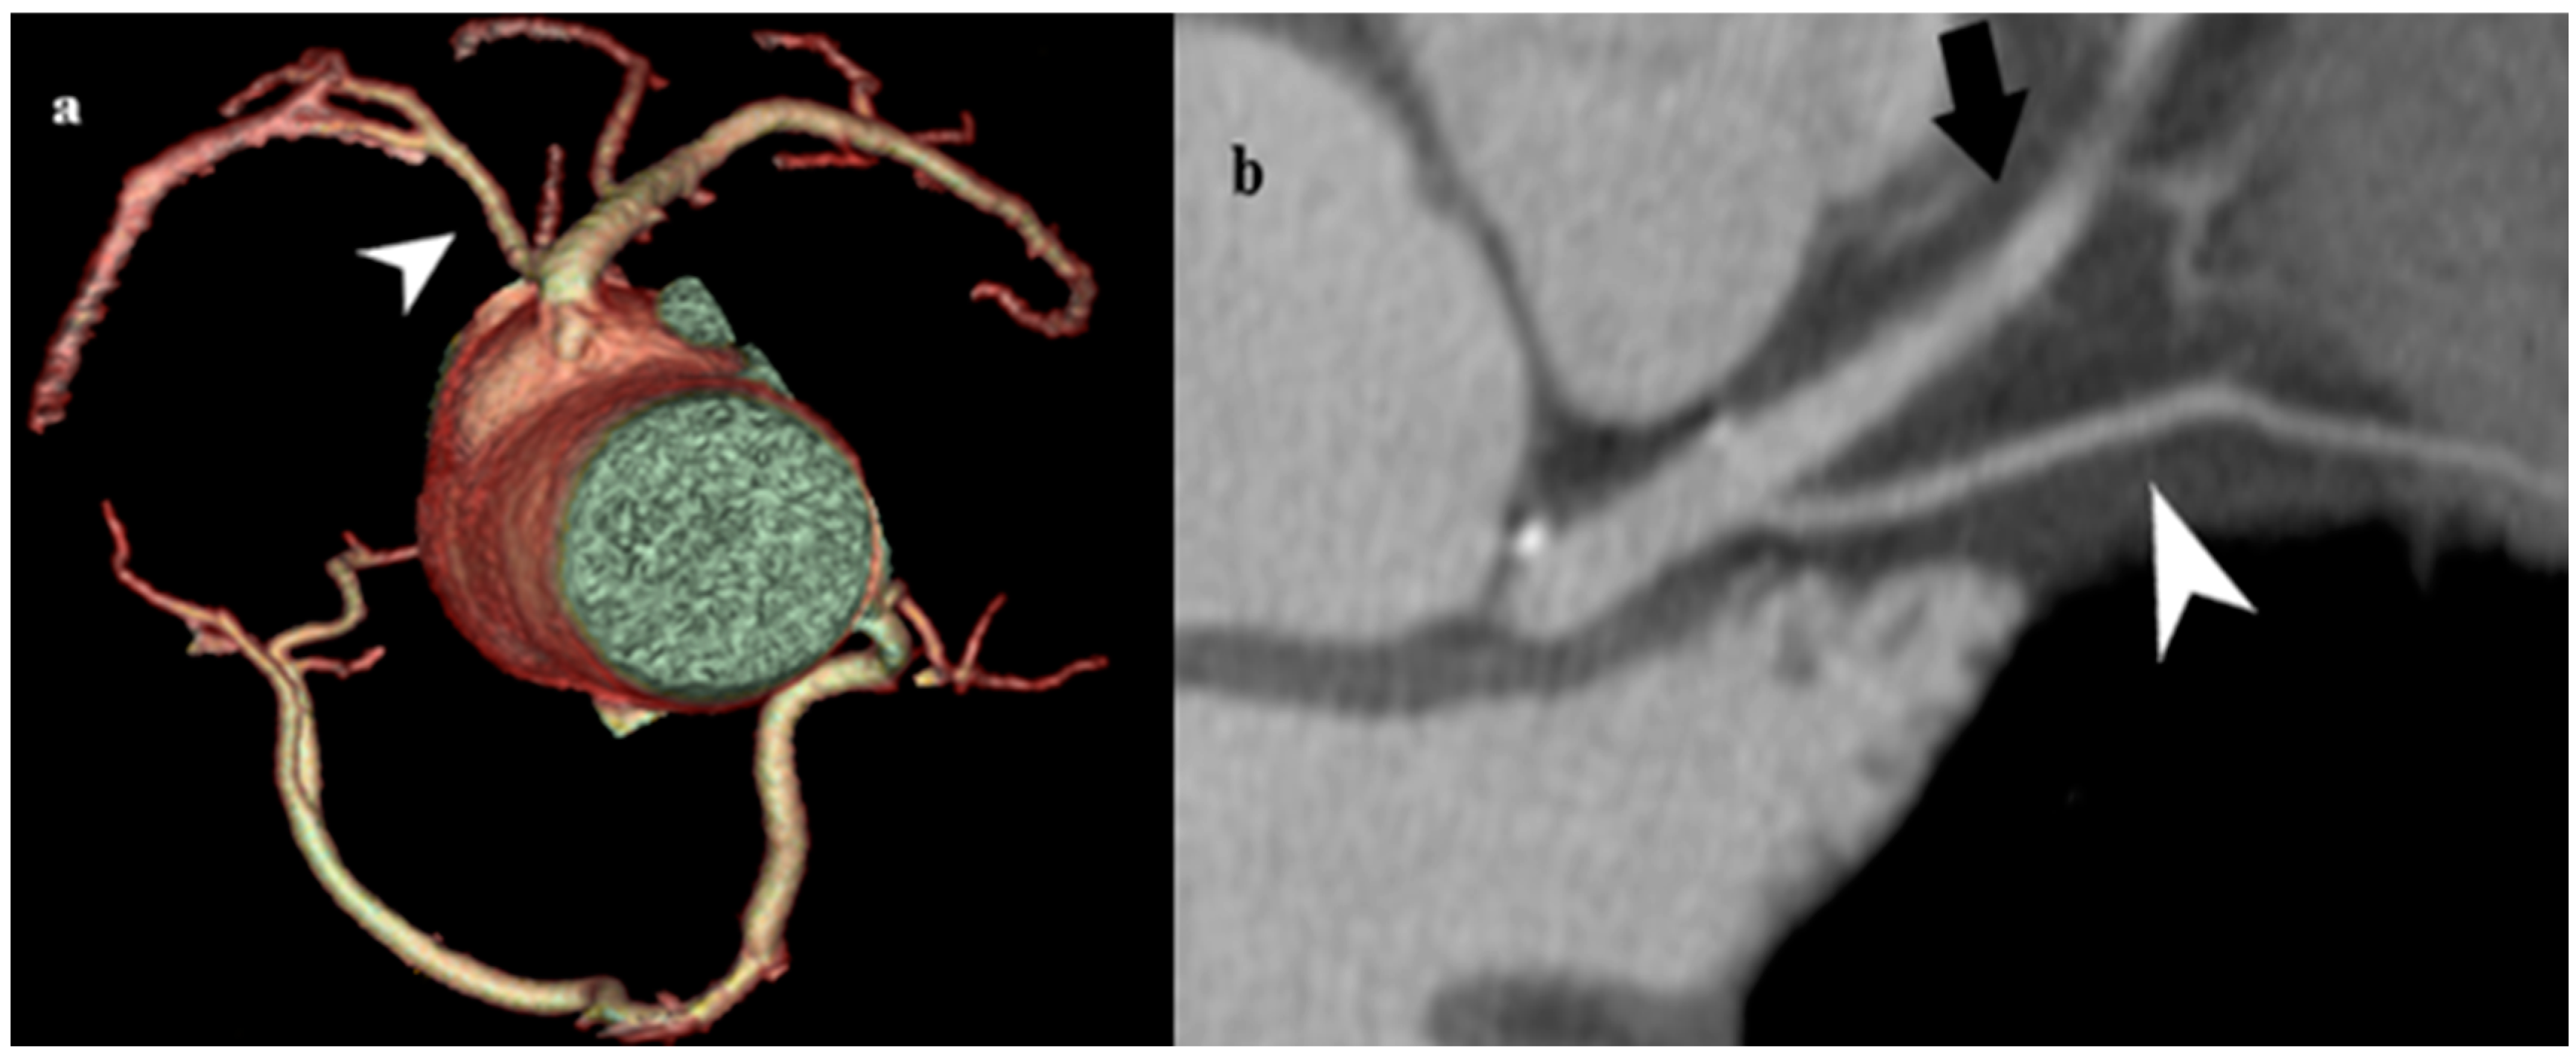

3.2.2. Double Right Coronary Artery (RCA)

A double right coronary artery is defined as two right coronary arteries of similar diameters and flows arising from one or two separate openings in the right sinus of Valsalva (Figure 7), generally having complete regular branches that occur in single RCAs, each of which has its posterior descending artery (PDA) in its distal course [40]. Double RCA is an extremely rare coronary anomaly, with a prevalence ranging from 0.07 to 0.46%, depending on the report [41,42]. This variation is primarily benign and is discovered incidentally during radiological diagnosis in patients with cardiorespiratory symptoms. However, it is a predilection site for atherosclerosis, life-threatening arrhythmias, and myocardial infarction. In addition, it sometimes presents challenges to performing interventional coronary procedures [43]. The exact diagnosis of a double RCA cannot be readily established based on conventional coronary angiography, because it is difficult to distinguish this variation from the variation in the high branching of the right coronary artery. For this purpose, MDCT coronary angiography is the method of choice to differentiate between these aberrations.

Figure 7. Double RCA. (a) MDCT coronary angiography revealed two separate RCAs originating from a single ostium in the right sinus of Valsalva (arrow). Both RCAs gave off branches with typical courses and in parallel distribution. (b) Planar view of two separate RCAs originating from a single ostium in the right sinus of Valsalva (black arrow head). Though usually benign, this variation must be clearly identified to avoid misinterpretation during angiography and to guide stent placement or surgery.